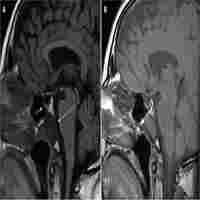

| Abstract | Background Graves’ disease is the commonest cause of thyrotoxicosis whilst thyrotropin (TSH)-producing pituitary adenomas (thyrotropinomas, TSHomas) are very rare and account for just 1–2% of all pituitary adenomas. Coexistence of a TSHoma and Graves’ disease has been very rarely reported. Here, we report a case of a patient whose initial presentation with primary thyrotoxicosis due to Graves’ disease, was subsequently followed by a relapse of thyrotoxicosis due to a probable TSHoma. Case A sixty-eight year old woman was referred to our department with classical features of thyrotoxicosis. Initial biochemistry confirmed hyperthyroxinaemia [free thyroxine (fT4) 20.4 pmol/L (reference range 7.0–16.0)] and a suppressed TSH [< 0.02mIU/L (0.50–4.20)]. A technetium pertechnetate uptake scan was consistent with Graves’ Disease. She was treated with carbimazole for 18 months and remained clinically and biochemically euthyroid. After stopping carbimazole her fT4 started to rise but TSH remained normal. Laboratory assay interference was excluded. A TRH stimulation test demonstrated a flat TSH response and pituitary MRI revealed a microadenoma. Remaining pituitary hormones were in the normal range other than a slightly raised IGF-1. An 11C-methionine PET/CT scan coregistered with volumetric MRI (Met-PET-MRICR) demonstrated high tracer uptake in the left lateral sella region suggestive of a functioning adenoma. The patient declined surgery and was unable to tolerate cabergoline or octreotide. Thereafter, she has elected to pursue a conservative approach with periodic surveillance. Conclusion This is a very unusual case of thyrotoxicosis caused by two different processes occurring in the same patient. It highlights the importance of considering dual pathology when previously concordant thyroid function tests become discordant. It also highlights a potential role of Met-PET-MRICR in the localisation of functioning pituitary tumours. |